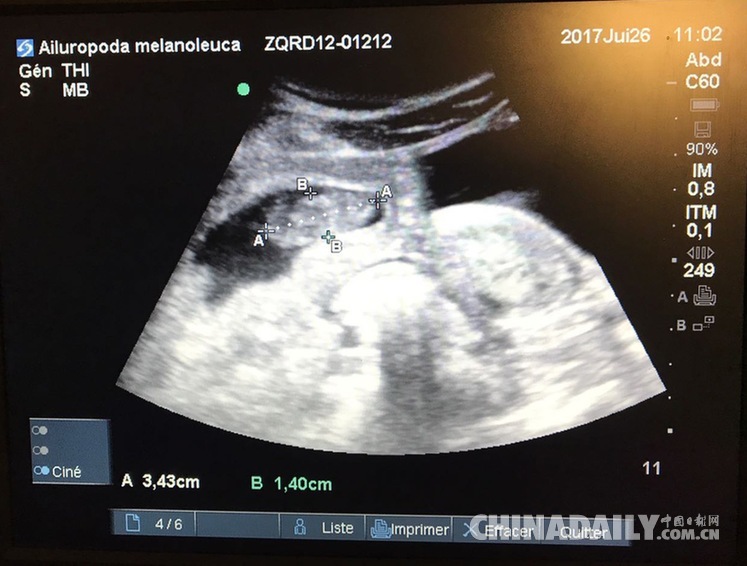

旅居法國熊貓產雙胞胎 一只存活狀態很好

9歲的大熊貓“歡歡”在接受最新B超檢查時發現懷上雙胞胎。